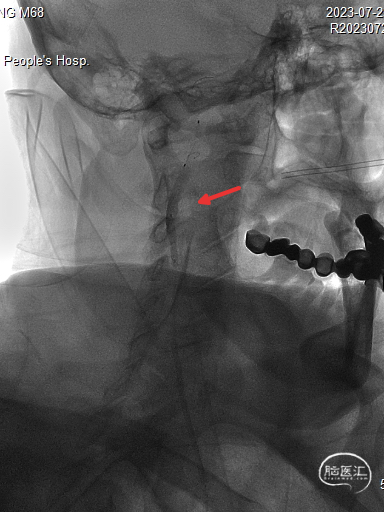

保护伞到位后释放(左图箭头),2.5*20mm通桥白驹®球囊以6atm扩张(右图箭头)。